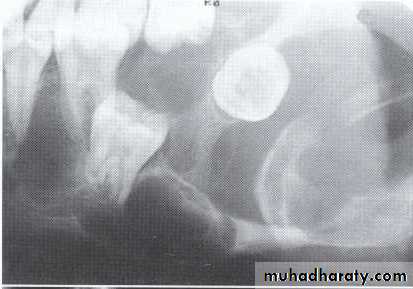

P. A. abscess

P. A. CystIs a cyst that remains after incomplete removal of the original cyst. The term residual is used most often for a radicular cyst that may be left behind, most commonly after extraction of a tooth.

*Persistent radiolucency in an area where a tooth has previously extracted.

• Residual cyst